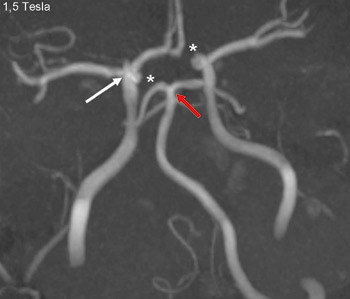

A person in his 20s with known migraine with aura developed infarcts in the right middle cerebral artery and both anterior fields of supply (Figure 1 shows a magnetic tomography diffusion weighted series). Cerebral computed and magnetic tomography with magnetic resonance angiography (MRA) after admission showed normal blood flow and no sign of dissection or vasculitis. Hemicraniectomy became necessary after development of malignant cerebral oedema. MR angiography the first postoperative day showed open arteries (Figure 2 shows an open carotid top (white arrow), normal basilar top (red arrow), and a non-closed circle of Willis, an anatomically normal variant (stars). Testing for illegal drug use, anticardiolipins, anti-nuclear antibodies, neurone antibodies and tumour markers was negative. Transoesophageal echocardiography showed a minimally patent foramen ovale, according to a cardiologic evaluation unlikely to be related to the episode. The patient developed severe brain stem involvement and MR angiography showed narrowing of the posterior branch of the basilar artery (arrows in Figure 3). Arterial vessel spasms were suspected retrospectively. The first suspected vessel spasm, in the right – middle/anterior branch, remained undocumented. The second, in the posterior branch of the basilar artery, was documented postoperatively (arrows in Figure 3). Images of several newly developed infarcts in the posterior circulation are not shown. Three weeks after the hemicraniectomy the angiogram was normalised (Figure 4).